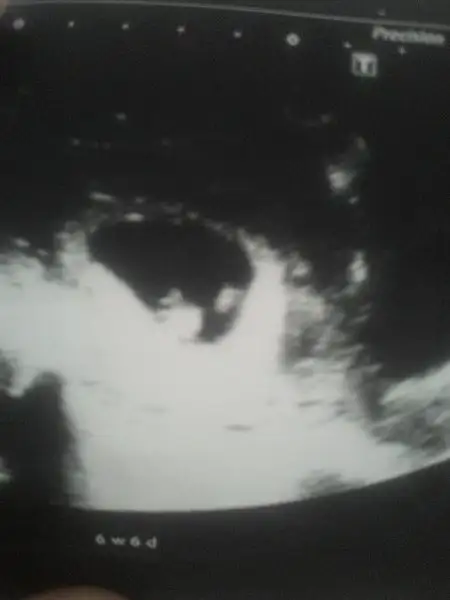

hayırlı olsun canım kese konumuna baktımısmıydın burda13 haftalık erkek dedi doktorum

canım sana zahmet varsa atabılırmısın tekrar kese konumu icin bu benımkıOrda da erkek diye tahmin etmişlerdi kız diyende olmuştu bi oğlum var ona arkadaş geliyo sükür

Doktorun tahminde bululnmadımıcanım sana zahmet varsa atabılırmısın tekrar kese konumu icin bu benımkıEki Görüntüle 2088211 buda 12haftalık usegEki Görüntüle 2088213